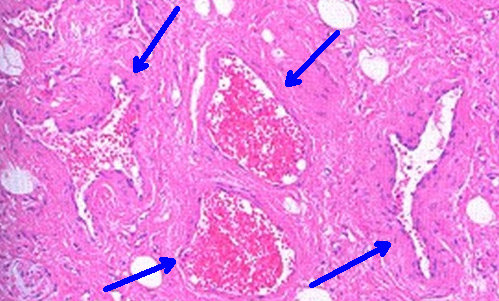

图4 静脉性血管瘤

生物学上所谓的肿瘤,应该是细胞过度增生(主要是数目增加)形成了“多余”的细胞团块,比如脂肪瘤是由过多的脂肪细胞组成,纤维瘤是由过多的纤维细胞组成。血管瘤看起来或摸上去象多余的一块肉团,却是由于一嘟噜紊乱的血管堆积而成(不是一种细胞),所以,本质上人们叫它“血管瘤”,却是一种杂乱血管团,生物学上叫“错构”,或者叫“畸形”。在名称上主要取决于这个杂乱的血管团主要由什么样的血管为主而命名,比如以静脉血管为主就叫做静脉性血管瘤、以毛细血管为主就叫做毛细血管性血管瘤、以动脉血管为主就叫做动脉性血管瘤。有的是以杂乱血管团中管腔的形状命名,比如管腔大小均匀看上去象海绵结构时叫海绵状血管瘤、如果是动脉管壁局部鼓突出来,犹如坑道中开挖了一个“猫耳洞”时叫动脉瘤,如果是动脉管壁中间被血液灌进来将管壁分开,犹如墙壁里多了个夹层时叫做夹层动脉瘤。